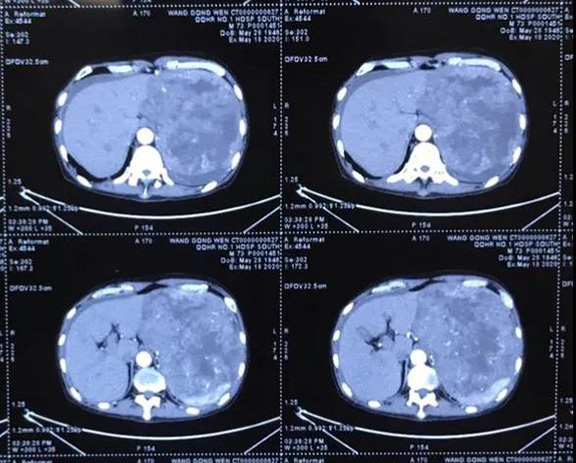

近日,一名年过古稀的患者上腹部胀痛、进食困难20余日,辗转数家医院就医未果,遂抱着试试看的态度来到普外科二病区。经过胃镜、增强CT检查后,提示患者胃占位性病变累及脾脏,胃间质瘤并肝脏转移可能性大。林国英立即组织科室成员进行了详细的术前讨论:患者诊断胃巨大间质瘤明确,考虑合并肝脏转移,理论上应口服药物进行治疗,待瘤体得到控制、减小后,再考虑二期手术治疗。但患者目前已无法进食,瘤体占满了左上腹腔,应及时进行手术治疗,争取切除肝脏转移瘤。但瘤体巨大,血运丰富,且与周围脏器关系密切,尤其脾脏脾门已经受到侵犯。为保证诊疗方案科学适宜,林国英立即组织影像科、输血科、麻醉科、手术室等相关科室专家进行了MDT会诊讨论,最终为患者“量身定制”了一套流程完善、技术完备的手术方案。

术中果然如术前预料般艰难。肿瘤来源于胃底,瘤体占满了整个左上腹腔,前上方与腹壁膈肌固定,左下方横结肠、胰腺、脾脏受压,推向下腹及后腹膜,右上方肝脏受压,推向右上腹,后方与后腹膜固定……整个可操作空间十分狭小,每一步操作都要求术者精细、确切。难度不止于此,瘤体后方几乎不可见,只能依靠手感进行钝行、锐性结合分离,困难程度可想而知。为保证手术的根治性,术中需联同脾脏一并切除,同时切除肝脏三处转移瘤。经历了6个小时的艰苦奋战,手术在多科室的通力配合下圆满完成,术后瘤体总重2400克。